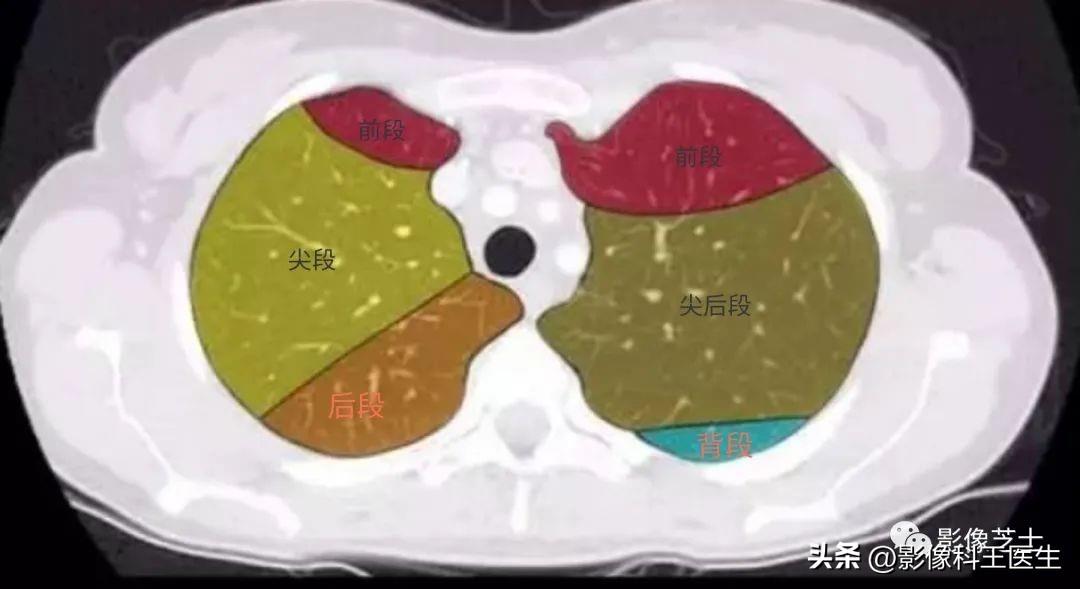

肺的分段